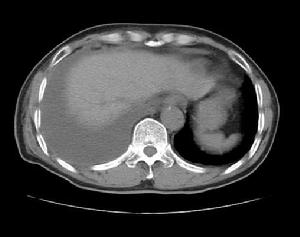

其他輔助檢查:CT、B超、核素、MRI、X線等有助於確定腫瘤的部位及性質。核素檢查對骨轉移可較早地提供明確診斷。